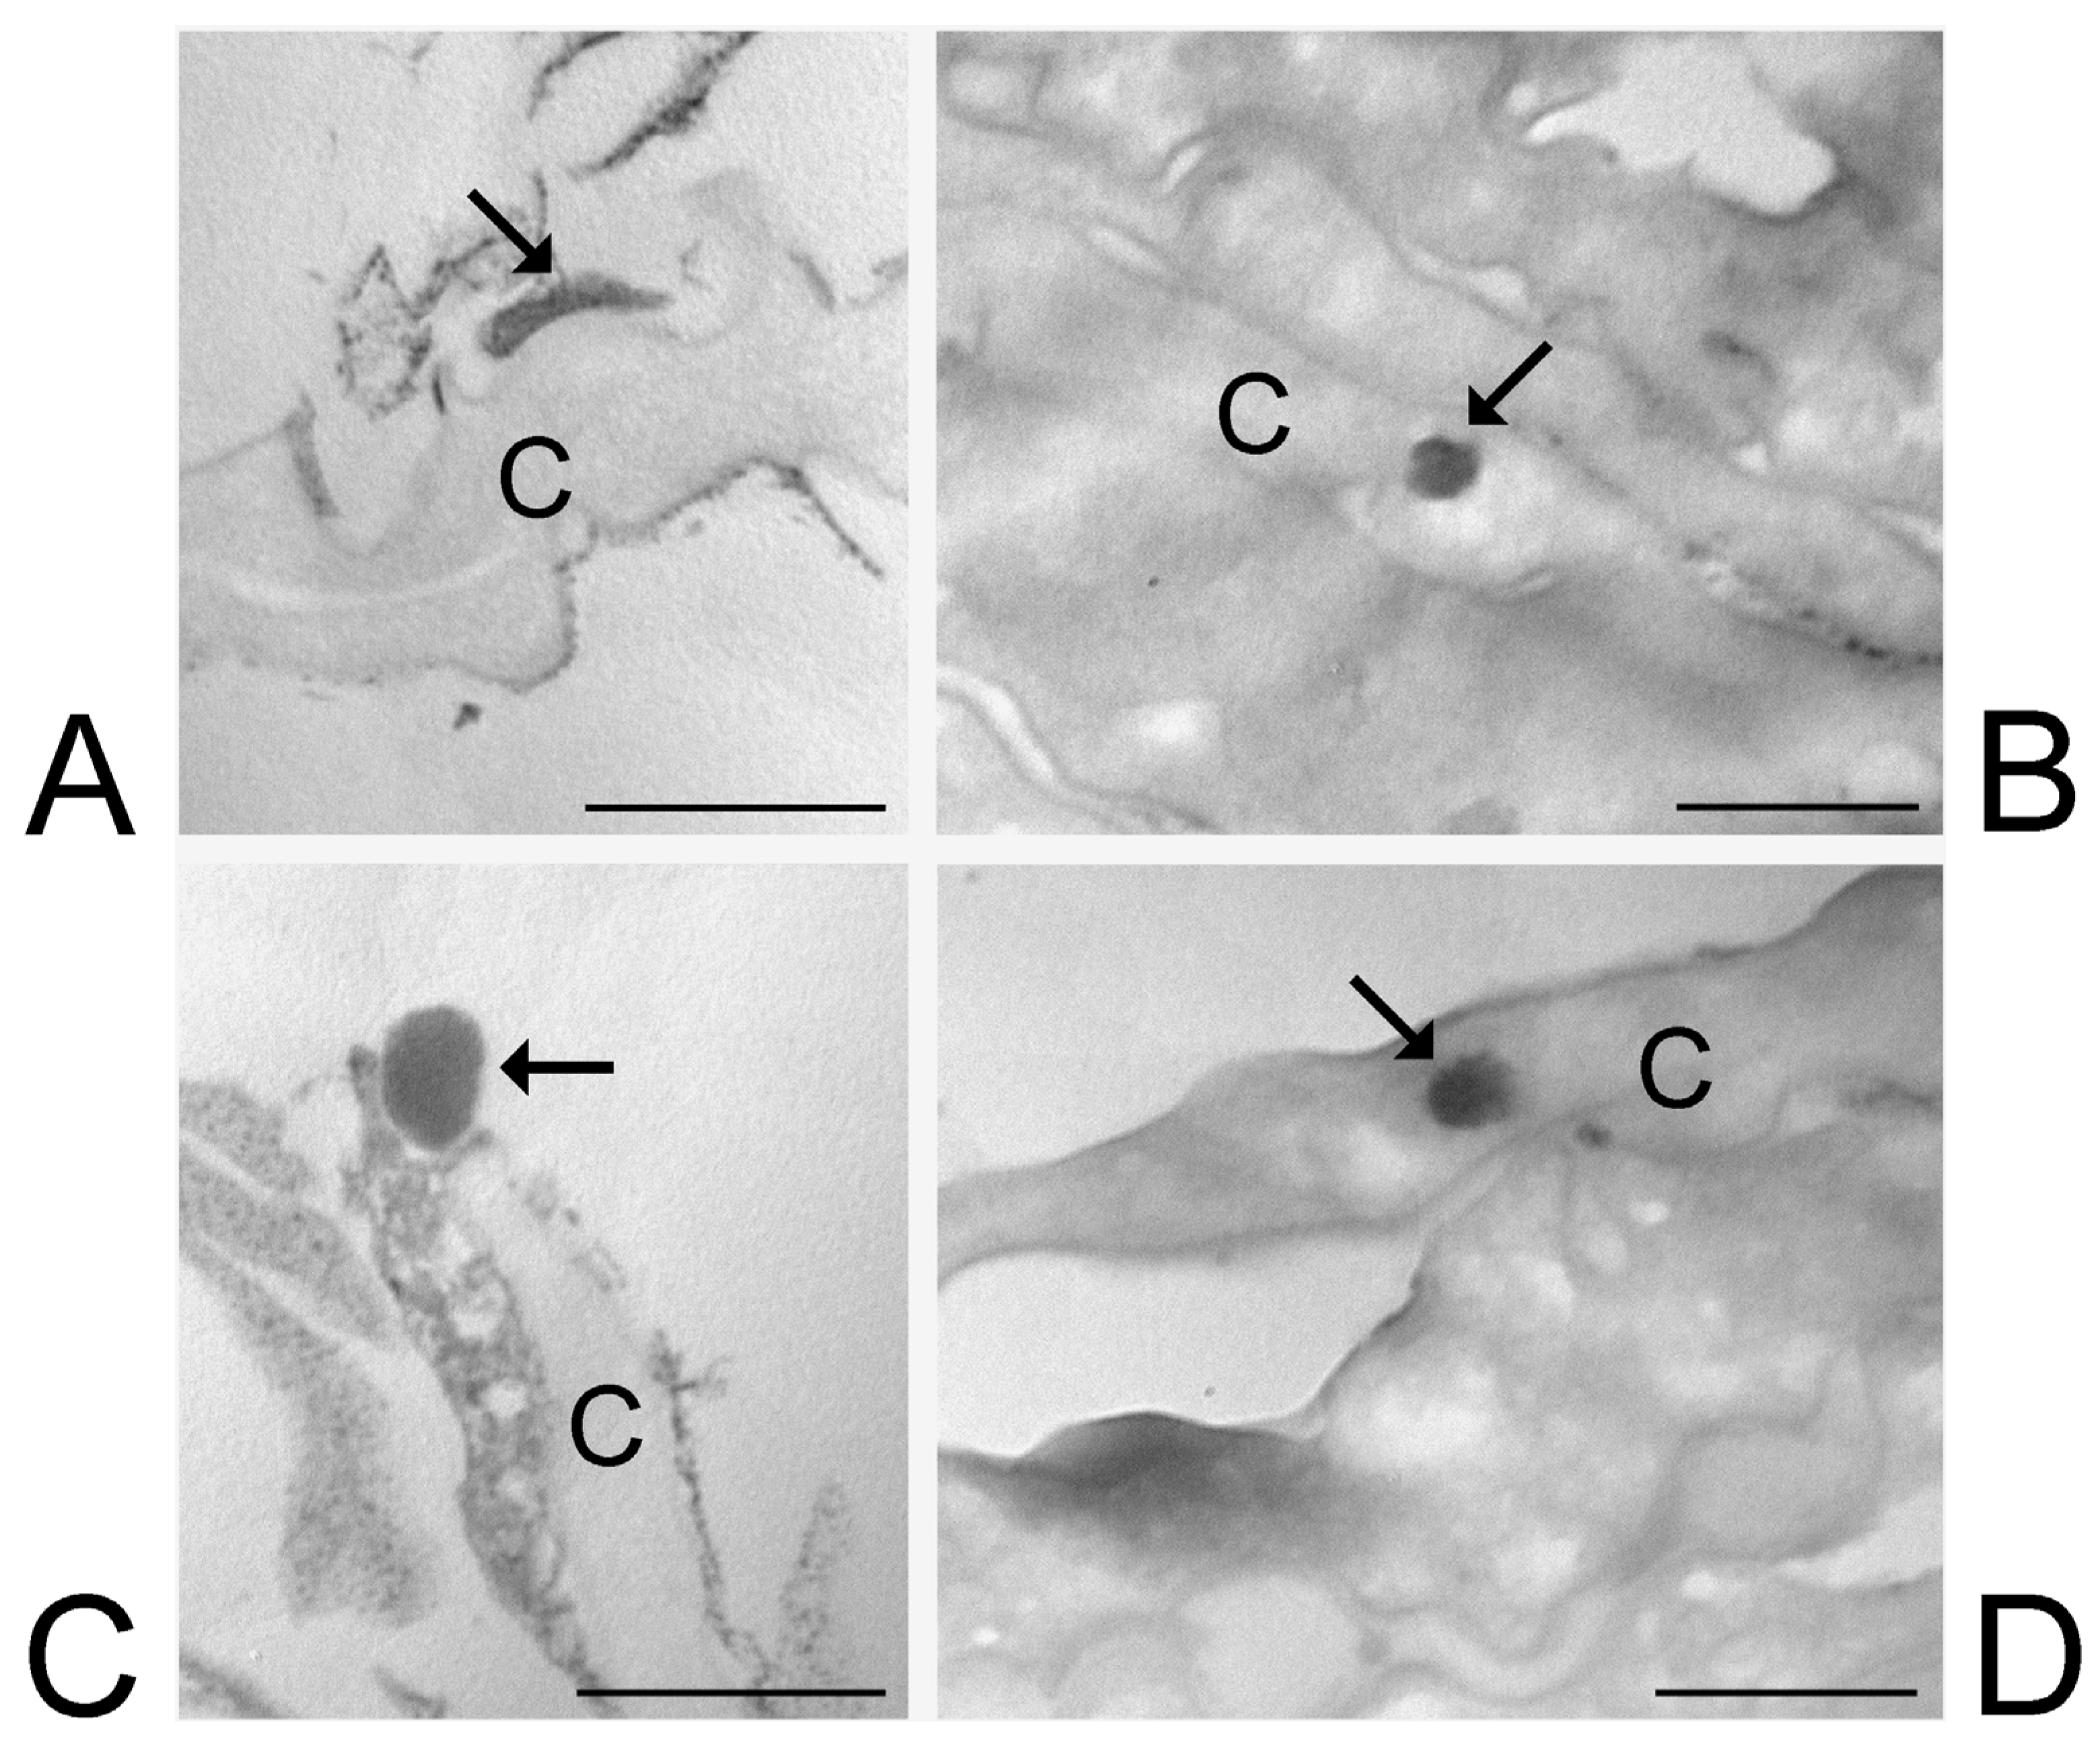

3.6. Transmission Electron Microscopy Analysis of Skin Treated with ETHO and LIPO